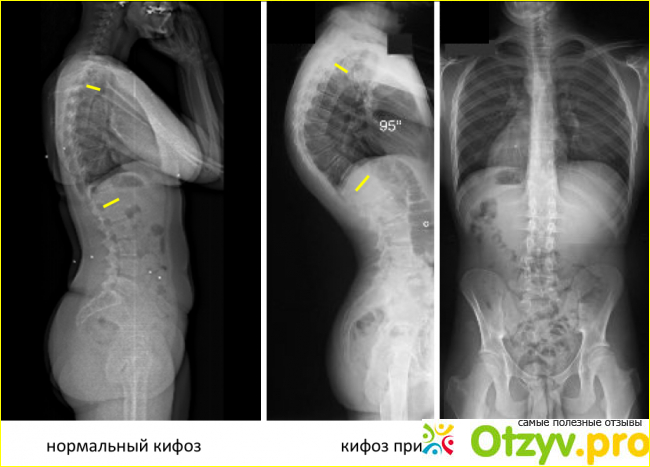

Болезнь Шейерман-Мау - прогрессирующая деформирующая дорсопатия, которая возникает, когда молодое тело активно растет. Эта патология представляет собой деформацию позвоночника, которая без своевременного лечения начинает прогрессировать и вызывает серьезные последствия.

Данное заболевание возникает из-за того, что из-за быстрого роста спинальных мышц у них нет времени на выздоровление, неспособное полностью поддерживать правильное положение спины. Подростки начинают опускаться, испытывая тяжесть, и из-за того, что также образуется костная ткань, деформация грудных позвонков еще не полностью происходит. Подобные изменения провоцируют приобретение позвоночника, что приводит к противоположной компенсирующей кривизне позвоночника в поясничной области, которая проявляется в поддержании баланса человеческого тела во время ходьбы.

- деформация позвонков - в грудной области позвонков, сплющенных с лицевой стороны, деформирующая, что вызывает утолщение продольной связки позвоночного столба в грудной области. Такие изменения сопровождаются ростом хрящевой ткани межпозвонкового диска в костную ткань позвоночника, что приводит к образованию грыжи Шморля;